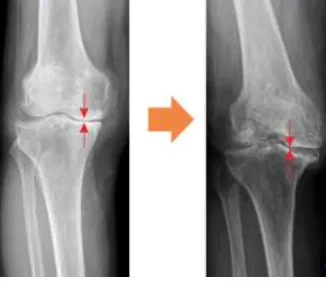

무릎 관절염은 많은 사람들에게 영향을 미치는 흔한 관절 문제 중 하나입니다. 이러한 질환이 있는 환자들은 적절한 운동을 통해 무릎 관절을 더욱 강화하고 통증을 완화하는데 도움을 줄 수 있습니다. 이 글에서는 무릎 관절염에 좋은 운동 10가지 및 주의사항에 대해서 자세히 살펴보겠습니다.

정기적인 무릎 관절염 운동은 기본적인 치료 방법이지만 오해에 기반한 운동 방법은 실제로 무릎 관절염을 악화시킬 수 있습니다.

무릎 관절염은 일상생활에 불편을 초래할 수 있지만 적절한 운동과 주의 사항을 준수하면 증상을 개선하고 생활의 질을 향상할 수 있습니다.